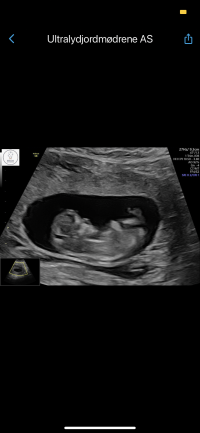

Ååh så kjekt! Lite som er bedre enn det!Så er uke 8+0, ble satt en uke frem Vis vedlegget 439187